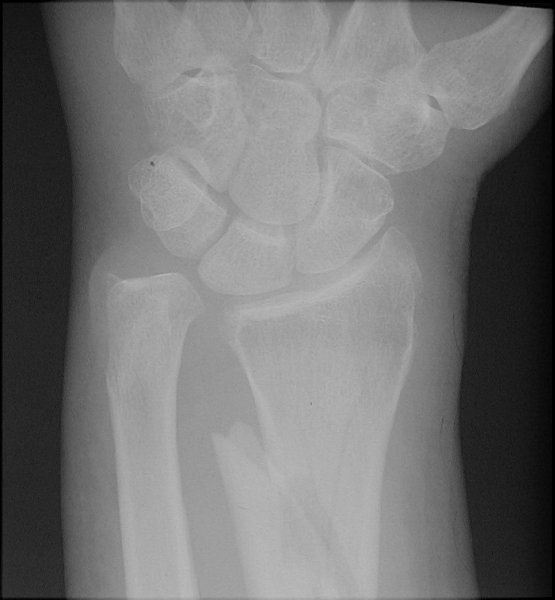

Return to Barton Fracture